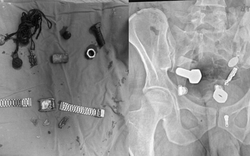

• Đang ăn sữa chua, người phụ nữ nuốt chiếc thìa dài 17cm vào bụng

Đang ăn sữa chua, người phụ nữ nuốt chiếc thìa dài 17cm vào bụng

Sức khỏe -

Một người phụ nữ đã vô tình nuốt phải một chiếc thìa dài 17cm khi con chó của cô nhảy lên đùi trong lúc cô đang ăn sữa chua.